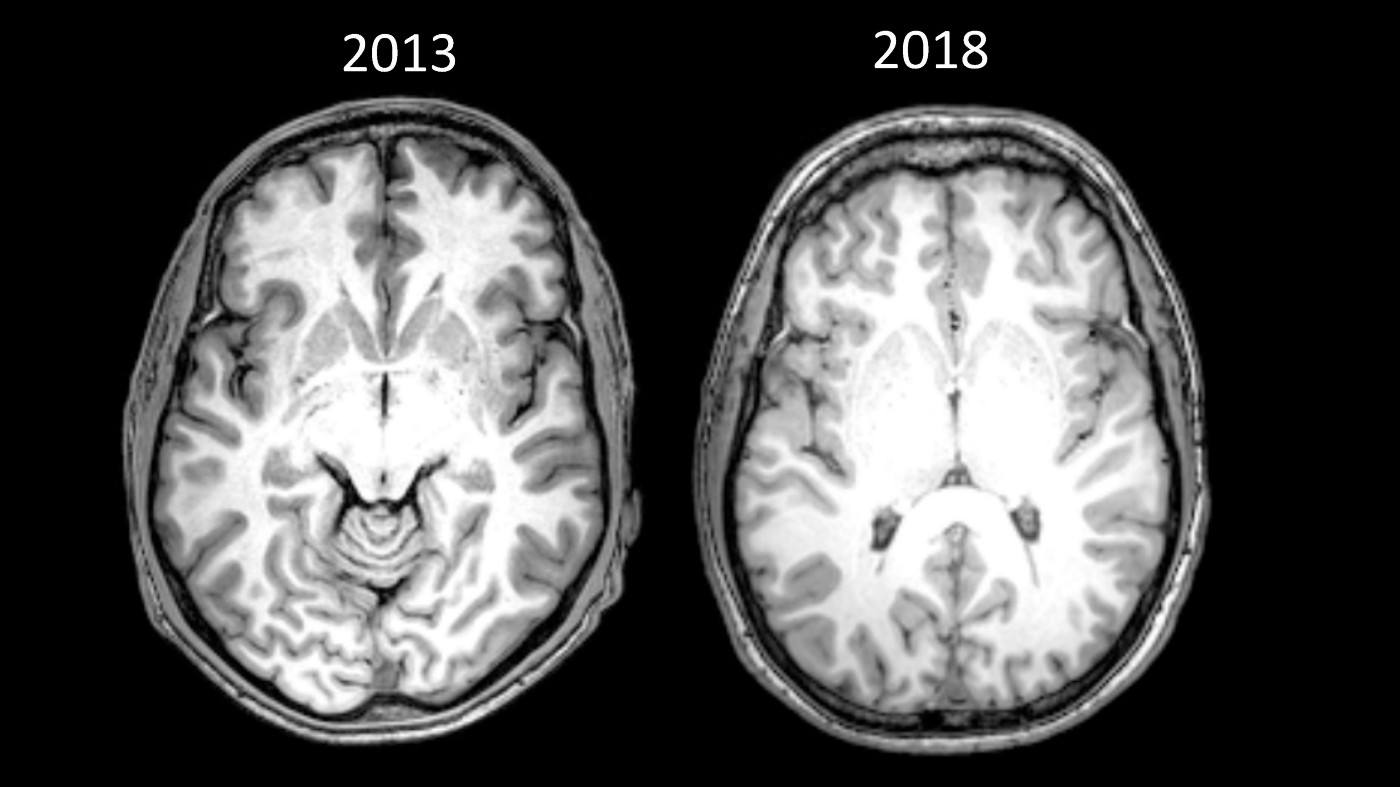

Ниже приведены снимки моего мозга. Левый стал частью исследования, проведённого в 2013 году на второй «чистый» день после 15 лет зависимости. Правый сделан в мае 2018 года, как часть документального фильма о стрессе.

Источник: необработанные снимки моего мозга в 2013 и 2018 годах. Здесь приведён разрез, показывающий переднюю спайку, стандартное анатомическое представление, используемое для сравнения разные сканов мозга. Было сложно сделать прямое сравнение разрезов, потому что использовались разные МРТ, а снимки сделаны в различных разрешениях

Мой мозг так сильно отличался, что человек, который его анализировал, не мог сравнить стандартные визуальные маркеры на глаз (выше привожу более техническое объяснение).

Так же пока сложно понять, что привело к таким разительным изменениям. Между сканами прошло четыре с половиной года, я значительно поменял многие аспекты жизни, включая диету, упражнения и сон [29]. Я вернулся в колледж и, конечно, перестал принимать героин.

Но я сам вижу, что преображение мозга стало следствием того, что я развил чуткость к моменту здесь и сейчас. Всё поменялось, когда мне рассказали об осознанности. Мне дали инструмент, чтобы победить моего злейшего врага — тревожность — это перевернуло игру.